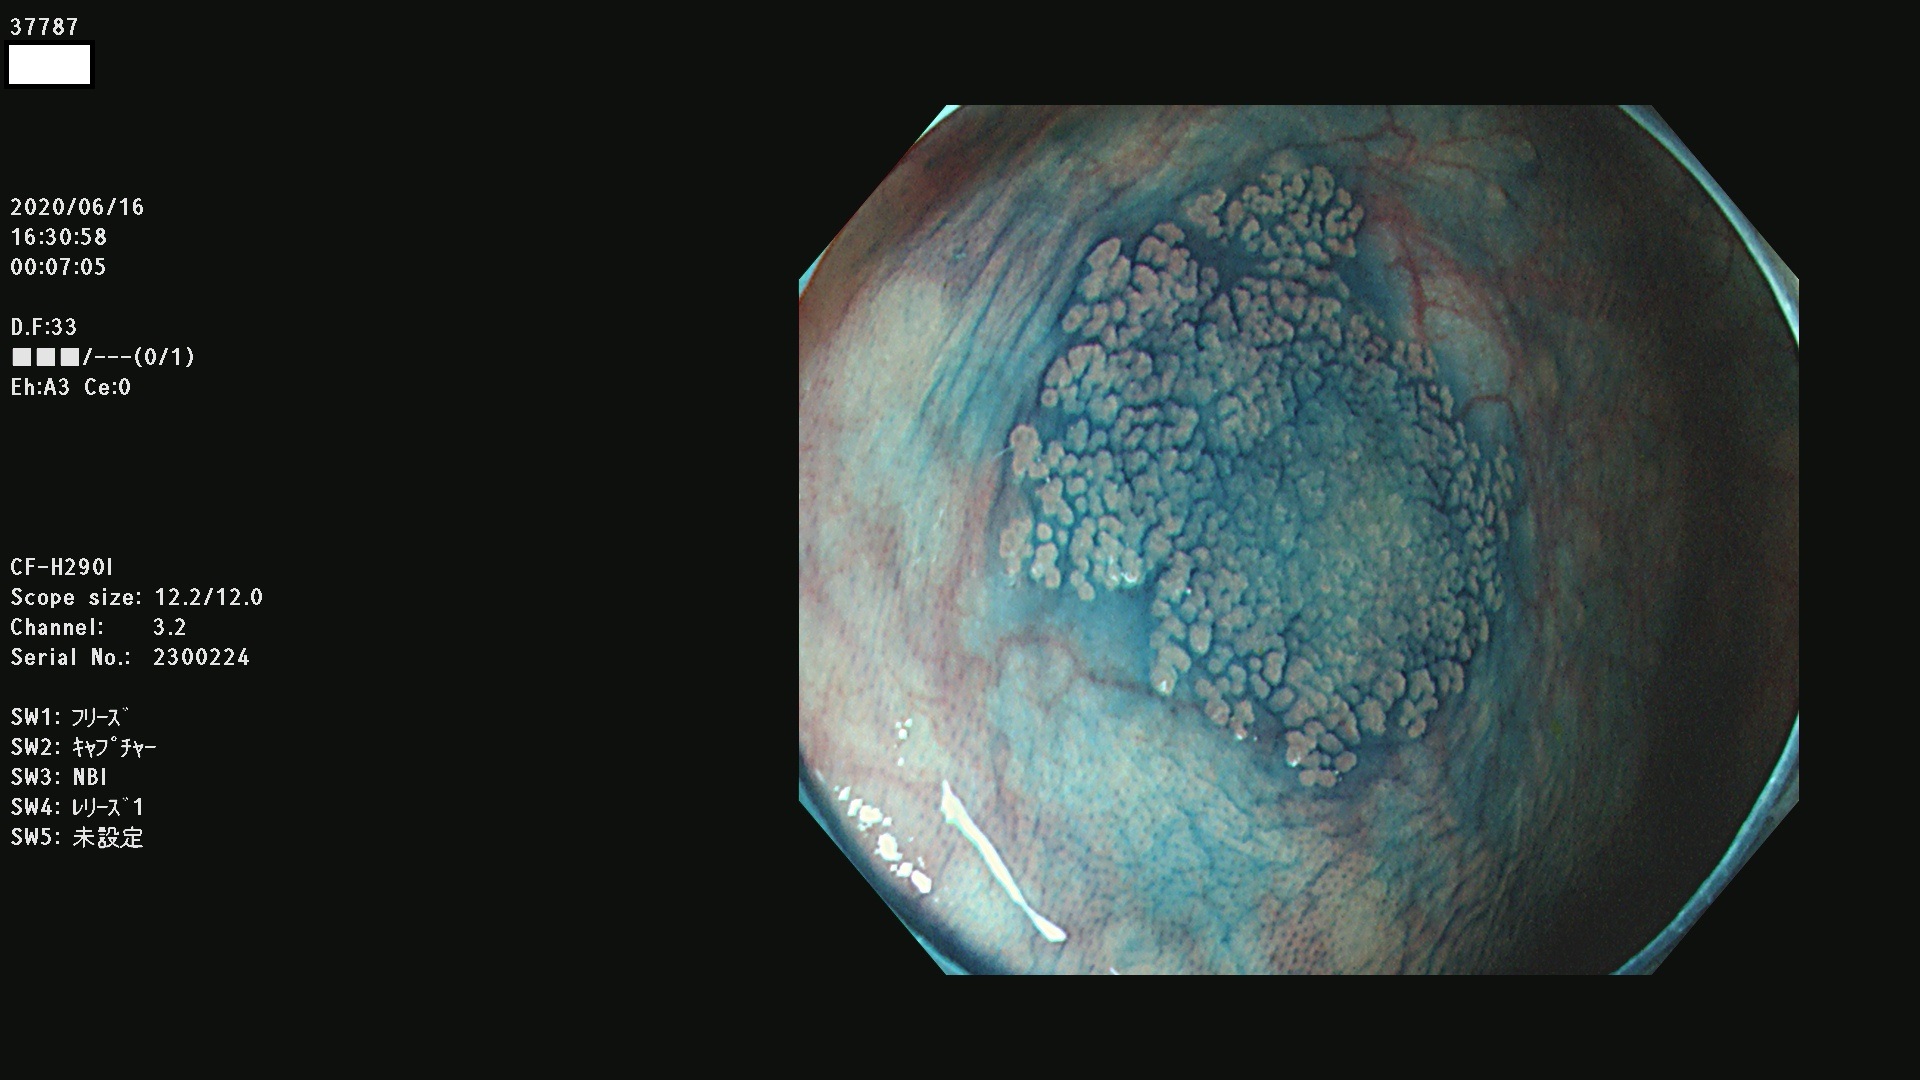

37700 37701 37702 37703 37704 37705 37706 37707(SSAPのみ) 37709 37711 37712 37715 37716 37717 37720 37722(SSAPのみ) 37724 37725 37726 37727 37728 37729 37731 37732 37733 37736(SSAPのみ) 37737 37739 37740 37741 37742 37744 37745 37748 37749 37750 37751 37752(SSAPのみ) 37753 37754 37755 37757 37758 37760 37761 37762(SSAPのみ) 37763 37764 37765 37766 37767 37768 37769 37771 37772 37774 37775 37776 37777 37780 37781 37782 37783 37784 37785 37787(SSAPのみ) 37788 37791 37792 37793 37794 37795 37799

発見困難で危険性の高い平坦型病変(上記100名より抽出)